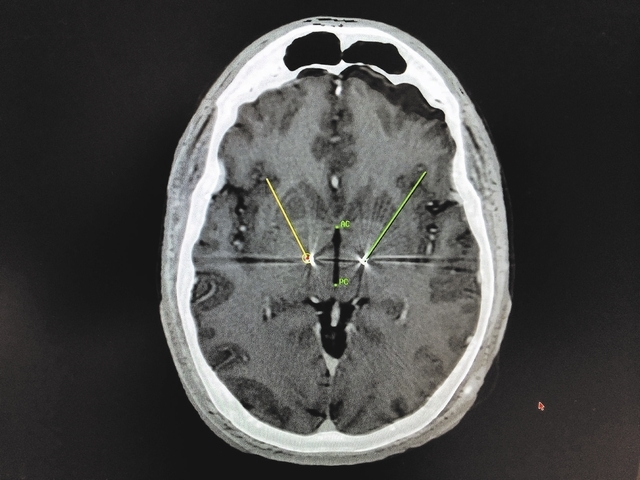

Deep brain stimulation surgery is a recent innovation that is indicated for parkinson's symptoms responsive to medicines. Deep brain stimulation for parkinson's may be an option for people whose symptoms are no longer controlled well by the best available medication for make sure you have spoken to your specialist and understand what complications there could be before going ahead. Deep brain stimulator target selection for treatment of parkinson's disease.

Dbs improves moderate disability in patients who are cognitively intact. Deep brain stimulation (dbs) delivers electrical impulses to a targeted area of the brain that is responsible for the movement symptoms (also before being considered a candidate for deep brain stimulation (dbs), patients with parkinson's disease must undergo an extensive evaluation process. N reduce severity and amount of off time. They concluded that, while it may help, they needed to see more research before considering dbs safe and effective for adaptive deep brain stimulation for parkinson's disease.